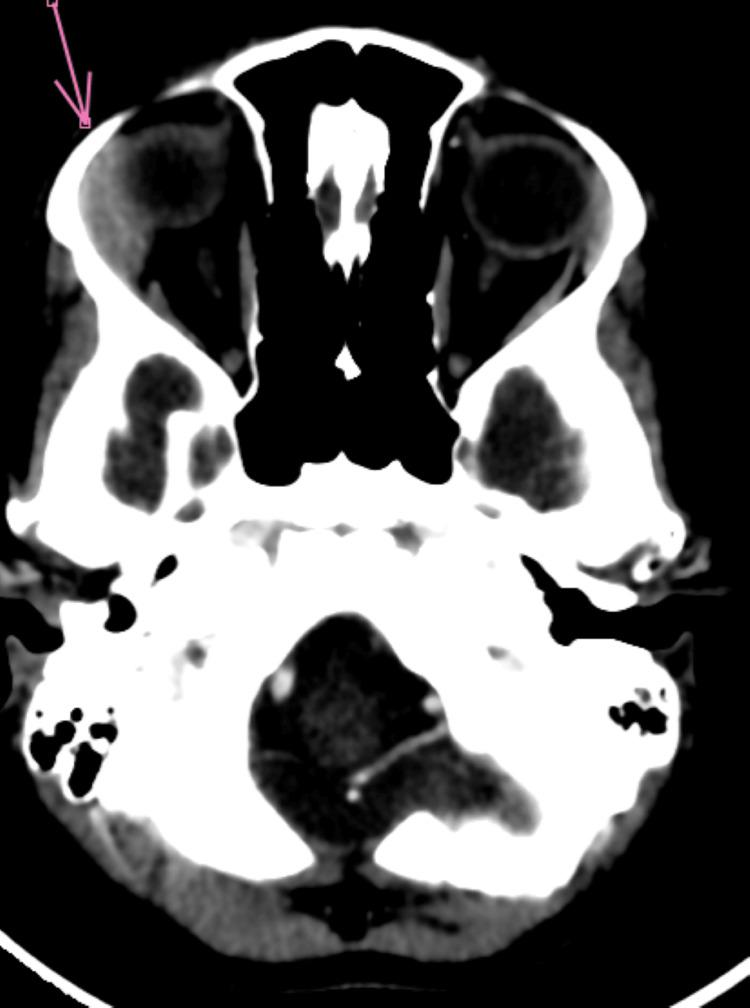

Acute myeloid leukemia (AML) is a malignant hematological condition characterized by the uncontrolled proliferation of immature myeloid cells in the bone marrow, which disrupts the normal production of blood cells. Although it is a relatively rare subtype of pediatric acute leukemia, it is a significant cause of leukemia-related mortality in children. Ocular involvement in acute leukemias, though uncommon, can be a revealing sign of the disease, sometimes presenting as either an initial or secondary manifestation, especially during relapse. We report the case of a five-year-old child presenting with progressive unilateral exophthalmos associated with fever, anemia, and chest pain, signs of general deterioration. Examinations revealed leukocytosis and circulating blasts, suggesting acute leukemia. A bone marrow aspirate confirmed the diagnosis of AML, subtype 2, with multilineage dysplasia. Orbital imaging showed exophthalmos associated with swelling of the lacrimal gland and infiltration of the extraconical fat. Chemotherapy treatment led to complete remission. Ocular manifestations, particularly exophthalmos, are frequently associated with AML and can indicate an aggressive form of the disease or extramedullary localization. Although this presentation generally has a poor prognosis, our case demonstrated a favorable outcome, which is exceptional in the literature. This case underscores the importance of considering leukemia in the differential diagnosis of unexplained exophthalmos in children and the need for rapid diagnostic testing, including bone marrow aspiration, to confirm the disease. Early recognition and appropriate treatment are crucial for improving prognosis.

急性髓系白血病(AML)是一种恶性血液疾病,其特征是骨髓中未成熟髓系细胞不受控制地增殖,这会扰乱血细胞的正常生成。尽管它是儿童急性白血病中相对罕见的亚型,但却是儿童白血病相关死亡的重要原因。急性白血病累及眼部虽然不常见,但可能是该病的一个提示性体征,有时表现为初始或继发表现,尤其是在复发期间。我们报告一例五岁儿童病例,该患儿出现进行性单侧眼球突出,并伴有发热、贫血和胸痛等全身状况恶化的体征。检查发现白细胞增多和循环原始细胞,提示急性白血病。骨髓穿刺确诊为AML,2型,伴有多系发育异常。眼眶成像显示眼球突出伴泪腺肿大和眶锥外脂肪浸润。化疗治疗导致完全缓解。眼部表现,尤其是眼球突出,常与AML相关,可提示疾病的侵袭性形式或髓外定位。虽然这种表现通常预后较差,但我们的病例显示了良好的结果,这在文献中是例外情况。该病例强调了在儿童不明原因眼球突出的鉴别诊断中考虑白血病的重要性,以及进行包括骨髓穿刺在内的快速诊断检测以确诊疾病的必要性。早期识别和适当治疗对改善预后至关重要。